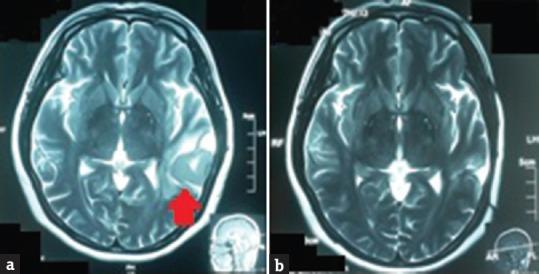

We report a rare case of a young female with primary brain fibrosarcoma, and to the best of our knowledge, we believe that only <50 cases have been reported or described worldwide so far. Fibrosarcoma is a malignant neoplasm, in which histologically the predominant cells are fibroblasts that divide excessively without cellular control and they can invade local tissues or metastasize. Primary central nervous system fibrosarcomas are very aggressive neoplasms and generally have a poor prognosis. This tumor is either from sarcomatous transformation of a meningioma or arises within the brain parenchyma. Our patient, a 48-year-old woman, who presented with progressive speech disorder over the period of 4 months, showed a left temporoparietal lesion with surrounding edema and local mass effect. Total surgical resection was achieved. Histopathology revealed classical fibrosarcoma features and secondary screening revealed no other distant lesion as diagnosis of primary brain fibrosarcoma was established. This case is deemed to be extremely rare because most reports claim that recurrence is within 6 months with poor prognosis; however, this patient is currently recurrence-free at 3 years. This would suggest of the possibility for a relook into this disease's course and recurrence rate when complete excision is achieved. Due to extreme rarity of these tumors, more comparative studies will be needed to improve the disease outcome.

我们报告了一例罕见的原发性脑纤维肉瘤年轻女性病例,据我们所知,到目前为止,全球仅报告或描述了不到50例。纤维肉瘤是一种恶性肿瘤,从组织学上看,主要细胞是成纤维细胞,它们不受细胞控制地过度分裂,可侵犯局部组织或发生转移。原发性中枢神经系统纤维肉瘤是极具侵袭性的肿瘤,通常预后较差。这种肿瘤要么是脑膜瘤的肉瘤样转化,要么起源于脑实质内。我们的患者是一名48岁女性,在4个月内出现进行性言语障碍,表现为左颞顶叶病变,伴有周围水肿和局部占位效应。实现了肿瘤全切。组织病理学显示为典型的纤维肉瘤特征,二次筛查未发现其他远处病变,从而确诊为原发性脑纤维肉瘤。该病例被认为极为罕见,因为大多数报告称复发在6个月内,预后较差;然而,该患者目前3年无复发。这表明在实现完全切除后,有可能重新审视这种疾病的病程和复发率。由于这些肿瘤极为罕见,需要更多的对比研究来改善疾病的治疗结果。